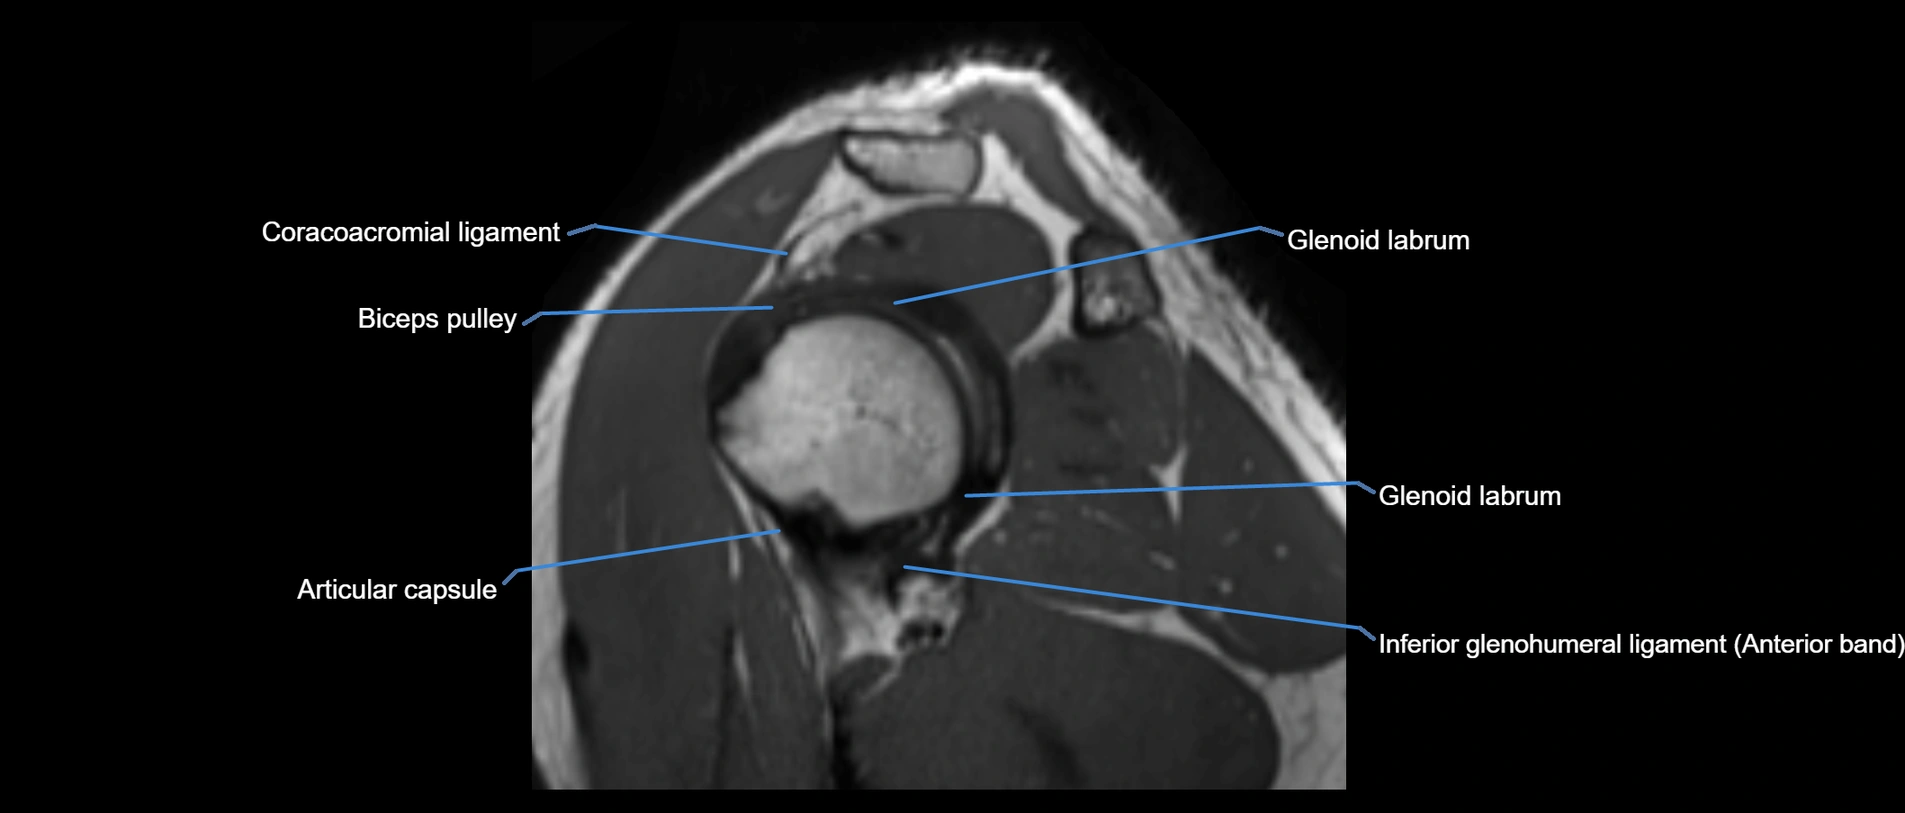

MRI images

image